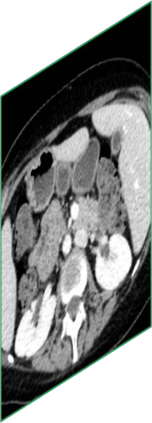

Due to the constraints of the imaging device and high cost in operation time, computer tomography (CT) scans are usually acquired with low intra-slice resolution. Improving the intra-slice resolution is beneficial to the disease diagnosis for both human experts and computer-aided systems. To this end, this paper builds a novel medical slice synthesis to increase the between-slice resolution. Considering that the ground-truth intermediate medical slices are always absent in clinical practice, we introduce the incremental cross-view mutual distillation strategy to accomplish this task in the self-supervised learning manner. Specifically, we model this problem from three different views: slice-wise interpolation from axial view and pixel-wise interpolation from coronal and sagittal views. Under this circumstance, the models learned from different views can distill valuable knowledge to guide the learning processes of each other. We can repeat this process to make the models synthesize intermediate slice data with increasing inter-slice resolution. To demonstrate the effectiveness of the proposed approach, we conduct comprehensive experiments on a large-scale CT dataset. Quantitative and qualitative comparison results show that our method outperforms state-of-the-art algorithms by clear margins.